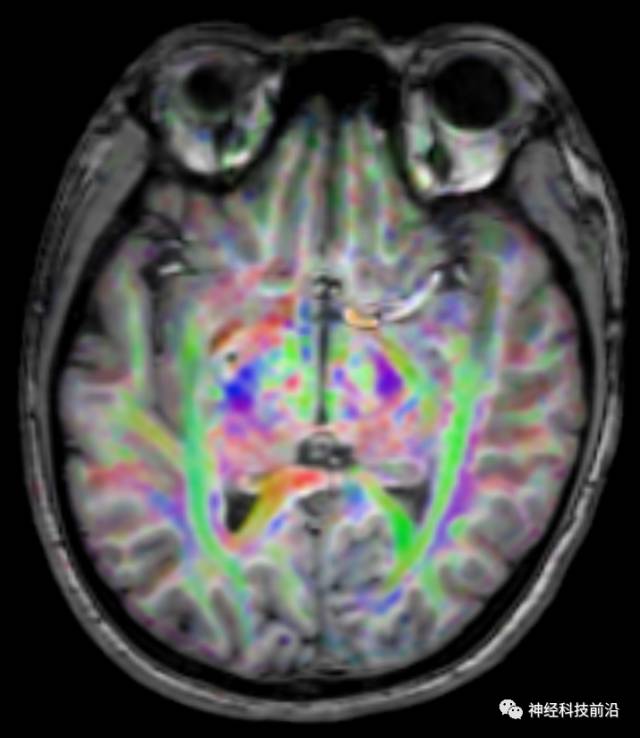

下面为皮质脑桥束的走形方位

皮质脑桥束与脑干高信号(黄色)纤维束

皮质脊髓束与皮质脑桥束的关系毗邻

上述纤维束与小脑中脚的位置毗邻